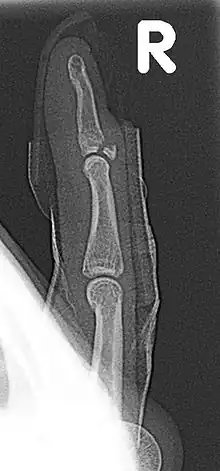

| Fracture of the dorsal base of the distal falange by extensor tendon avulsion (Busch fracture) | |

In medicine a Busch fracture[1] is a type of fracture of the base of the distal phalanx of the fingers, produced by the removal of the bone insertion (avulsion) of the extensor tendon. Without the appropriate treatment, the finger becomes a hammer finger. It would correspond to the group B of the Albertoni classification.[2] It is very common in motorcycle riders and soccer joggers, caused by hyperflexion when the tendon is exercising its maximum tension (the closed hand tightening the clutch lever or the brake lever).[3][4]

A Busch fracture, showing the characteristic mallet finger

Busch fracture mechanism: because the bit of bone attached to the tendon has broken off, the tendon can't extend the finger tip